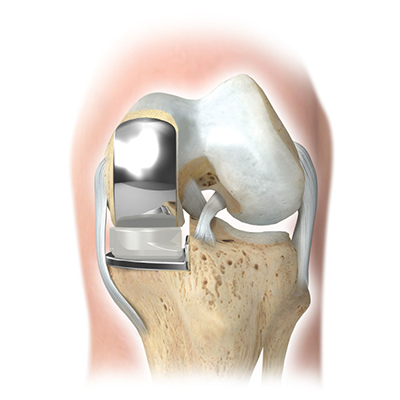

Knee joint is exposed using a midline incision on the front of knee. Joint is exposed after separating the muscle and cutting through the capsule. The worn and damaged surface of bone and cartilage from lower end of femur (thigh bone) and upper end of tibia (shin bone) are removed and shaped to accept the prosthetic metal implants. A plastic spacer is again inserted between these two components. The soft tissues around the knee are carefully balanced to correct the alignment of the joint and optimize the function of knee